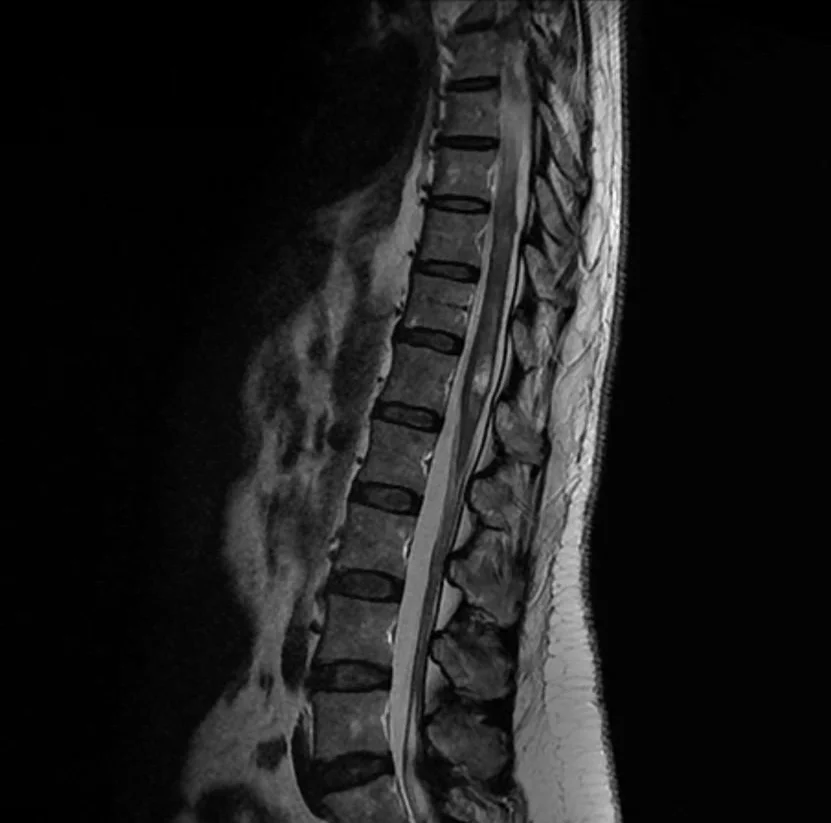

Le diagnostic est fait classiquement sur l’ IRM de la moelle épinière avec injection de Gadolinium. En fonction de la localisation et de l’aspect de la tumeur, votre neurochirurgien pourra vous demander de compléter ce bilan par un scanner et/ou une artériographie médullaire, qui pourra être organisée dans le service de Neuroradiologie interventionnelle situé dans le bâtiment Babinski (Pr Clarençon).